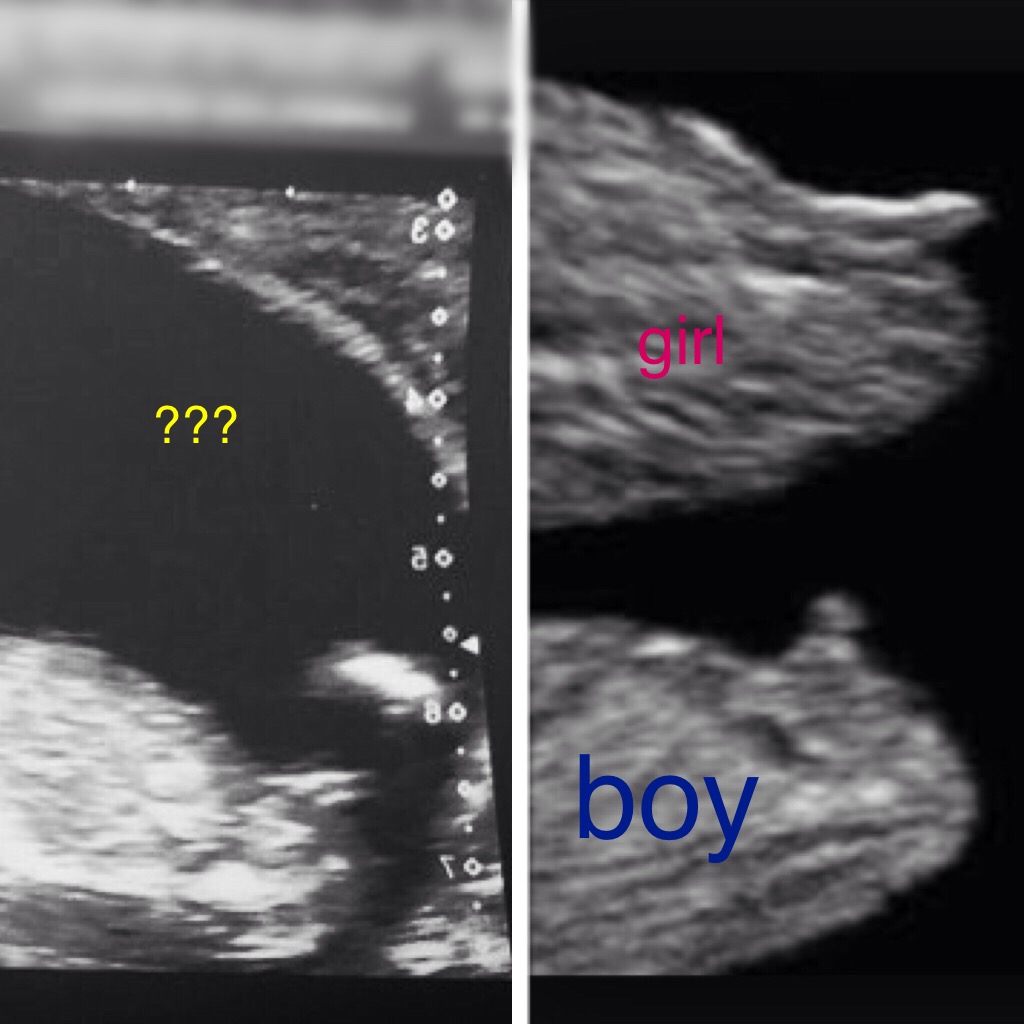

Hi I'm new to gender dreaming and have been obsessed with looking at my babies nub as soon as I heard about..... Could any of you loverly ladies help me and have a look at my babies nub I was on a different site and got mixed boy and girls?? I really don't know what to think??? thank you so much in advance 12w +6days Attachment 32397Attachment 32398